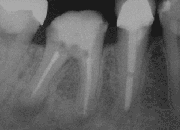

![]() X-ray of a tooth after root end surgery | |

A root end surgery, also known as apicoectomy (apico- + -ectomy), apicectomy (apic- + -ectomy), retrograde root canal treatment (cf. orthograde root canal treatment) or root-end filling, is an endodontic surgical procedure whereby a tooth's root tip is removed and a root end cavity is prepared and filled with a biocompatible material. It is an example of a periradicular surgery.

In an apicoectomy, only the tip of the root is removed. This is in contrast to root resection, where an entire root is removed, and hemisection, where a root together with its overlying portion of the crown are separated the rest of the tooth and optionally removed.[2]